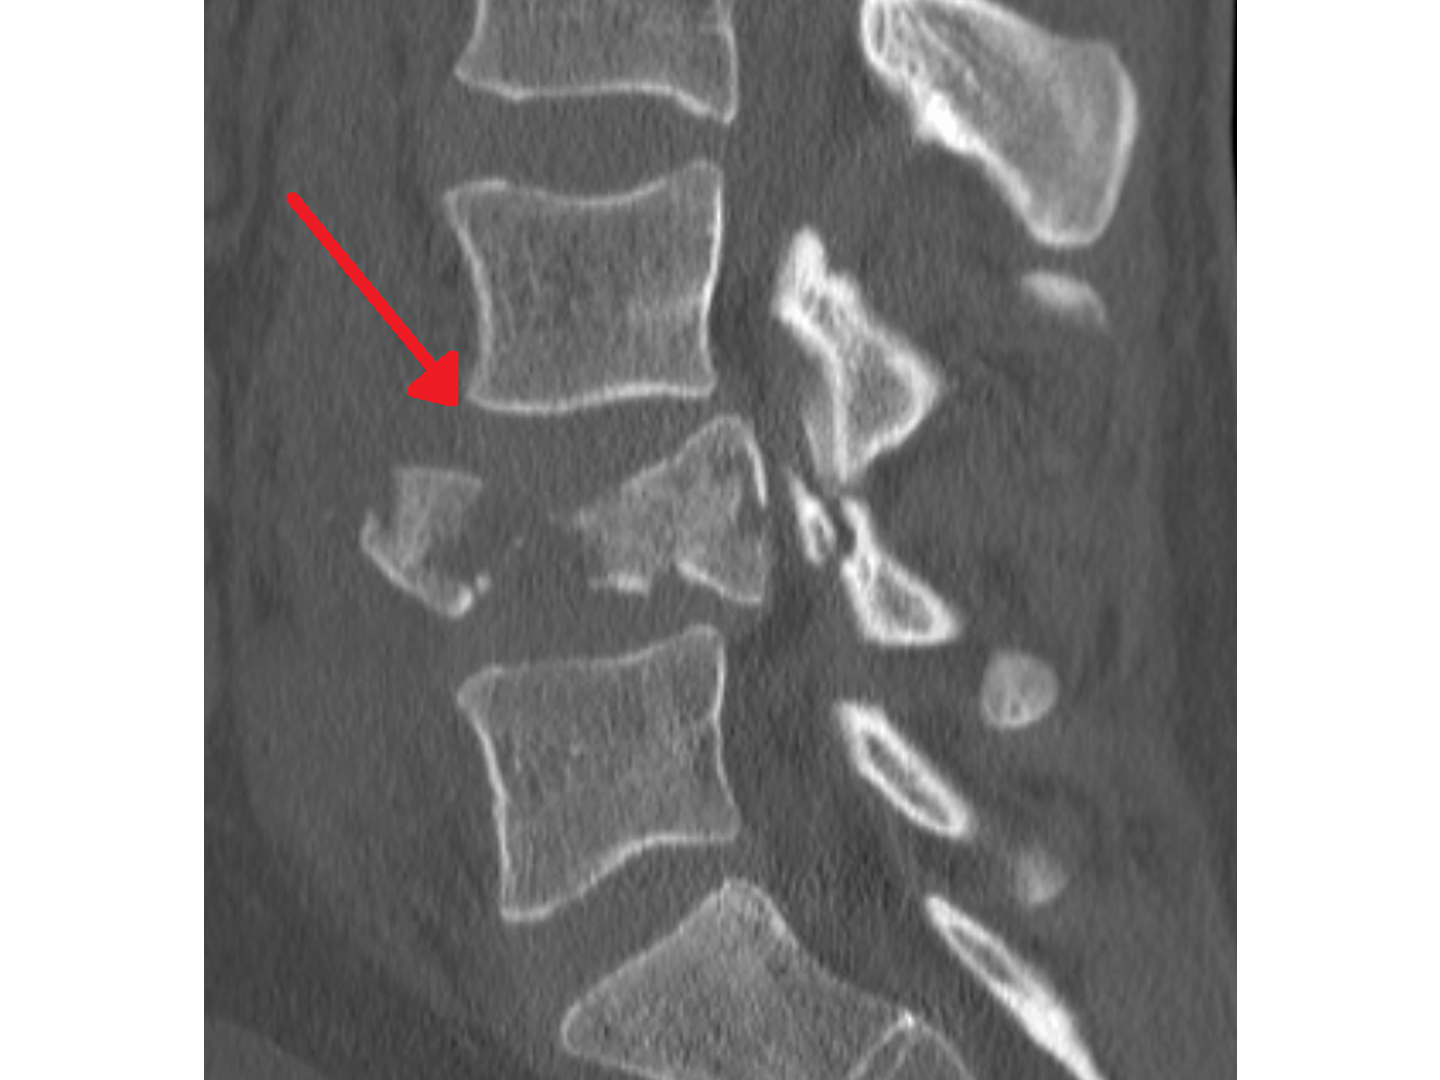

Verursacht wird sie durch ein Hyperextensionstrauma. Eine weitaus häufigere Ursache als das Erhängen sind Autounfälle, bei denen der Kopf eines unangeschnallten Fahrers frontal auf das Lenkrad schlägt. Siehe [[Abb. 789]] & [[Abb. 790]]